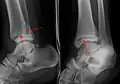

Une fracture triplane de la cheville vue sur une radiographie standard

Une fracture triplane de la cheville vue par TDM